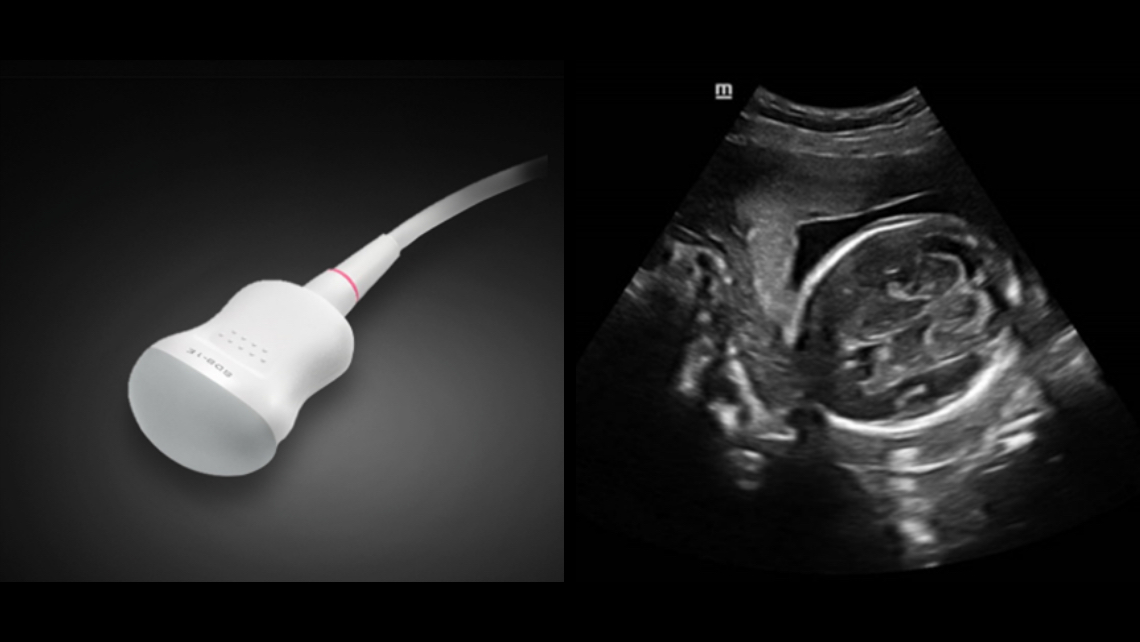

?chographe diagnostique

DC-40

Soins primaires avec Pure Crystal

Un design et une technologie au service de l'utilisateur

Images cliniques